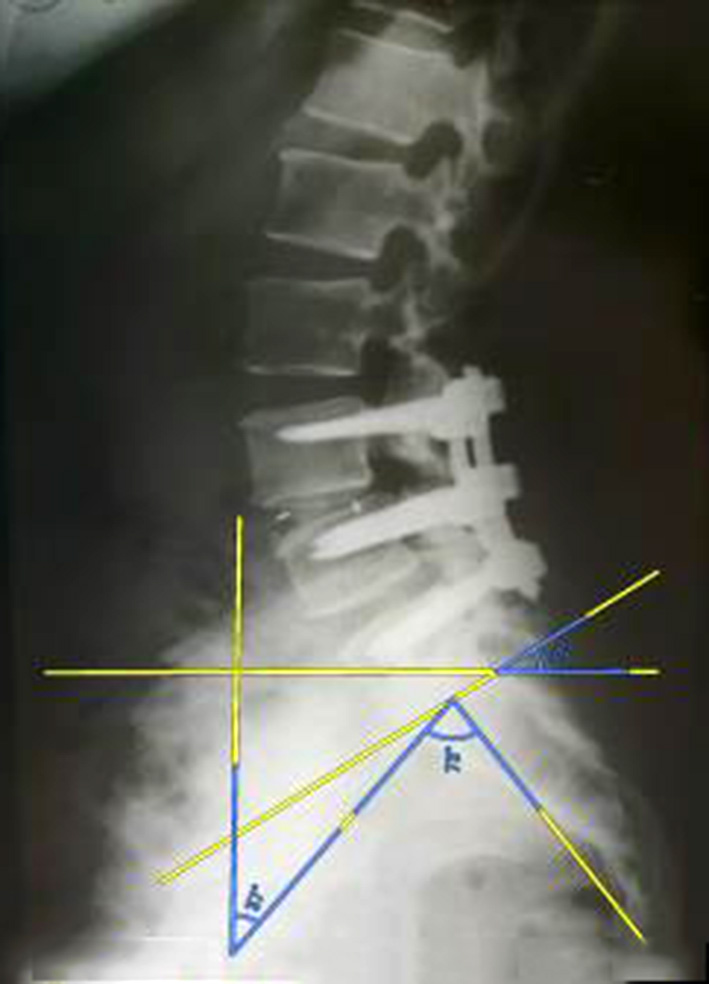

The clinical study involved 21 patients (15 women and 6 men), aged 32 to 68 years (median age – 56 (50; 65) years), divided into three groups: study group (n=4), where the author's technique of MIPIVS was applied (patent application No. a202302383 of 18.05.2023) (Fig. 3); comparison group (n=10), where the standard MIPIVS technique was used (Fig. 4); control group (n=7), where other interbody fusion techniques were employed (Fig. 5) .

Fig. 4. Radiographic control before and after surgery using the traditional minimally invasive posterior interbody vertebral stabilization (MIPIVS) technique